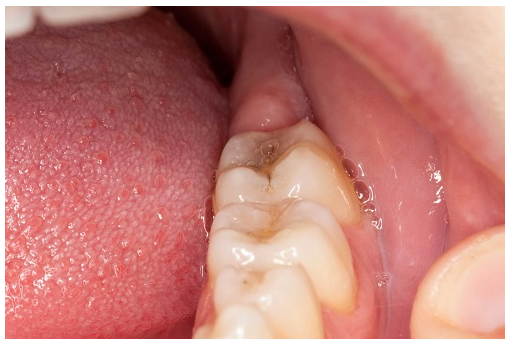

Trong khi một số lỗ sâu sẽ xuất hiện trên bề mặt răng dưới dạng áp xe hoặc lỗ hổng, một số khác sẽ trông như những đốm màu hoặc vết bẩn trên bề mặt của răng bị sâu. Dấu hiệu sâu răng cũng có thể là đốm màu đen, nâu hoặc trắng ở trên răng. Nếu những đốm màu này mềm hoặc dính, thì đó là dấu hiệu cho thấy lỗ sâu răng đang phát triển. Trong một số trường hợp, lỗ sâu răng có thể khiến toàn bộ chiếc răng tối màu hơn và làm tăng nguy cơ răng bị gãy, vỡ. Nếu bạn nhận thấy có những đốm màu lạ hoặc đổi màu trên răng, hãy đến gặp nha sỹ để được đánh giá tình trạng sâu răng.

Sưng tại lợi có thể là một triệu chứng của tình trạng sâu răng, mặc dù tình trạng sưng có thể sẽ không gây đau đớn. Nếu bạn có lỗ sâu răng rất sâu, nó có thể gây tổn thương hoặc hoại tử dây thần kinh và điều này sẽ gây ra tình trạng nhiễm trùng tại dây thần kinh đó, dẫn đến sưng lợi. Một số người cảm thấy lợi mình bị sưng nhưng lại không thấy đau, nhưng đó vẫn là tình trạng nhiễm trùng. Hãy liên lạc với nha sỹ nếu bạn nhận thấy một vùng lợi của mình bị sưng vì đó có thể là dấu hiệu của sâu răng hoặc viêm lợi.